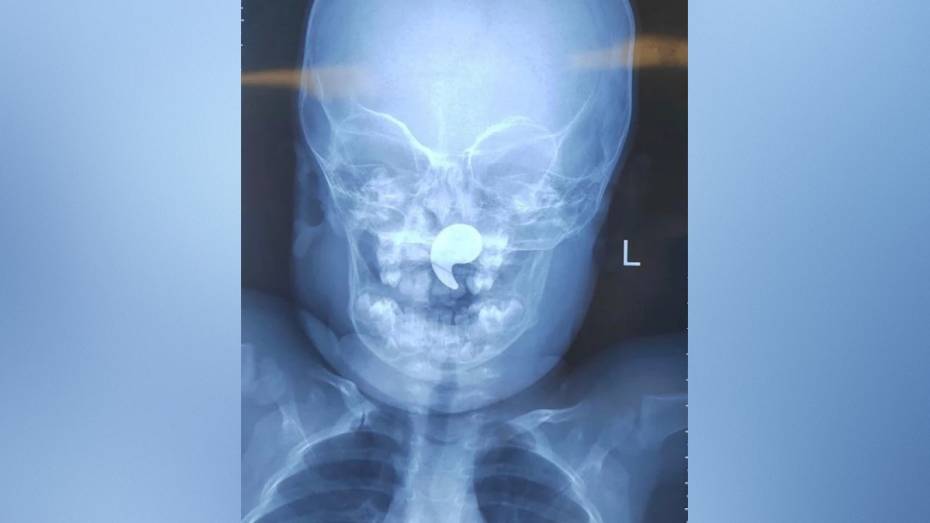

Врачи областной детской больницы №1 достали из носоглотки полуторагодовалой девочки магнит. Ребенок жаловался на боль в горле и отказывался от еды. У малышки также заметили активное слюноотделение. Родители обратились к дежурному ЛОР-врачу. Об этом сообщили в пресс-службе министерства здравоохранения Воронежской области в четверг, 26 марта.

Выяснилось, что девочка играла магнитом в форме запятой. Мать ребенка заметила, что малышка начала давиться, и попыталась извлечь инородное тело пальцем. Так магнит сместился в носоглотку.

Дежурный врач ЛОР-отделения Марина Перепечена под общей анестезией достала магнит под эндоскопическим контролем. Через сутки девочку выписали домой под наблюдение педиатра.